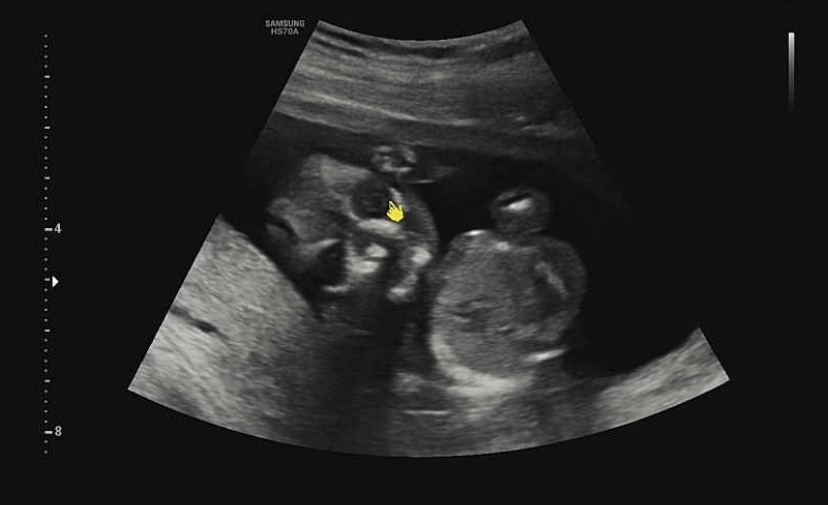

우리 아이는 각도법으로 반전 없이 딸로 판정!처음에는 남편을 닮은 아기가 좋을 것 같아서 아들을 원했지만 지금은 딸도 좋아 :- 3 예쁘고 잘 키워야지!

아직 10cm밖에 안 되는 아기가 발바닥도 있고 발가락도 5개 있다! 발바닥은 2센티밖에 안 되는데, 그렇게 작은데 발가락이 5개나 있다니!

그리고 나름대로 눈맞춤을 해준 아기!솔직히 내 아기인데 무서워서 놀랬어~! 해골 바가지인 줄 알았어. 아직 얼굴에 살이 없는 상태라 이런 모습이라고 한다. 선생님께서 안구도 잘 형성되어 있어요~ 하면서 가르쳐 주셨는데 무섭다..^^;; 빨리 살이쪄서 입체초음파때 얼굴을 보고싶어~!우리 둘 중 누구를 닮았는지 궁금해 🙂